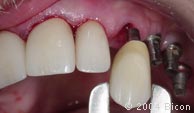

24. | 试戴一体化基台冠。 |